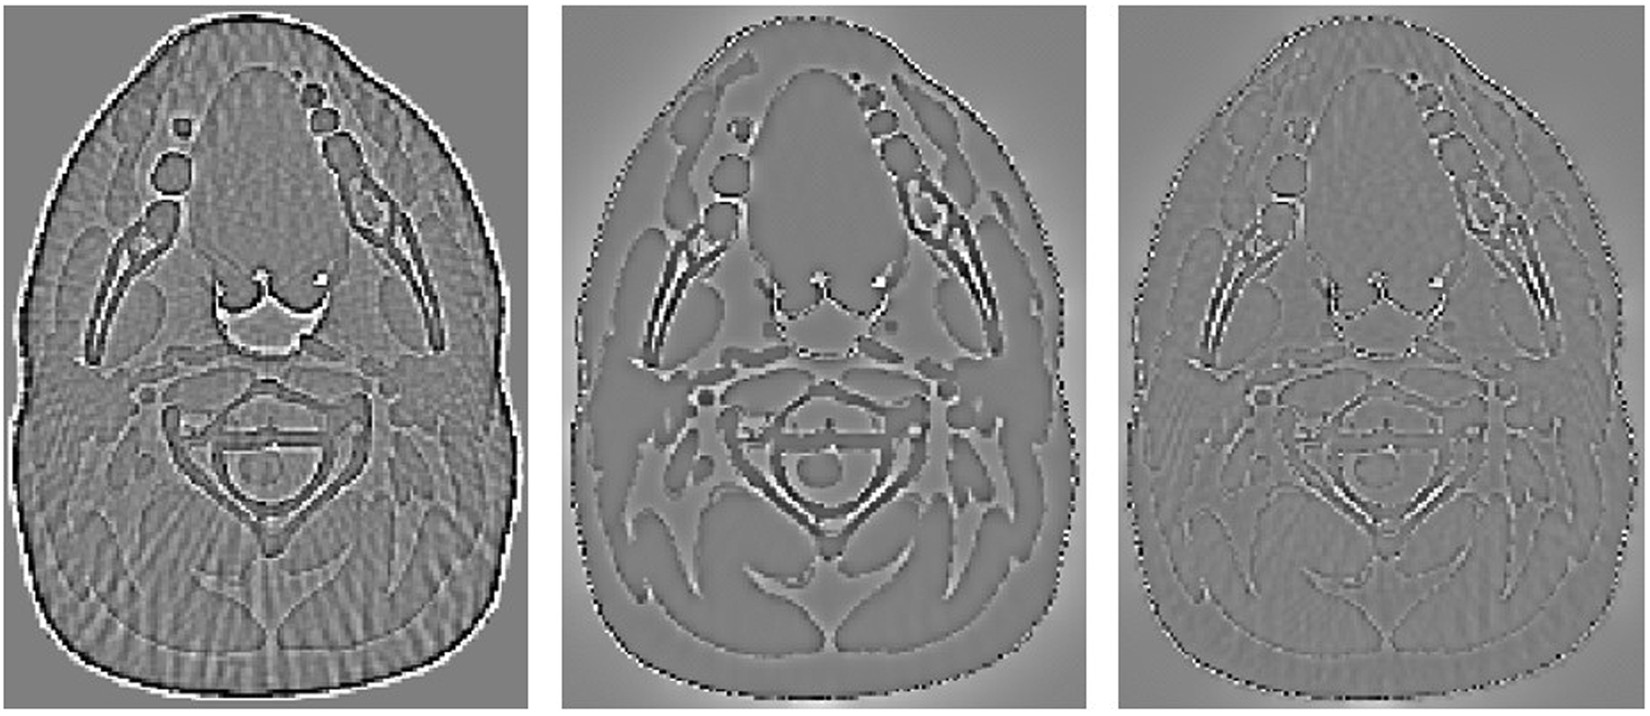

Figure 4

The residual image of the reconstructed results from Fig. 2. From left to right, the images are the residuals of results reconstructed by FBP, PWLS-TV and PWLS-TV-FR. The images are displayed in the window [−0.0015 0.0015].